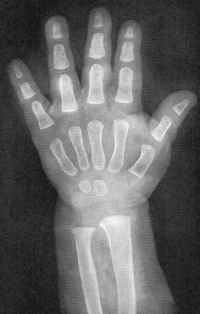

Sexo Masculino

Recém-Nascido

idade óssea - RN